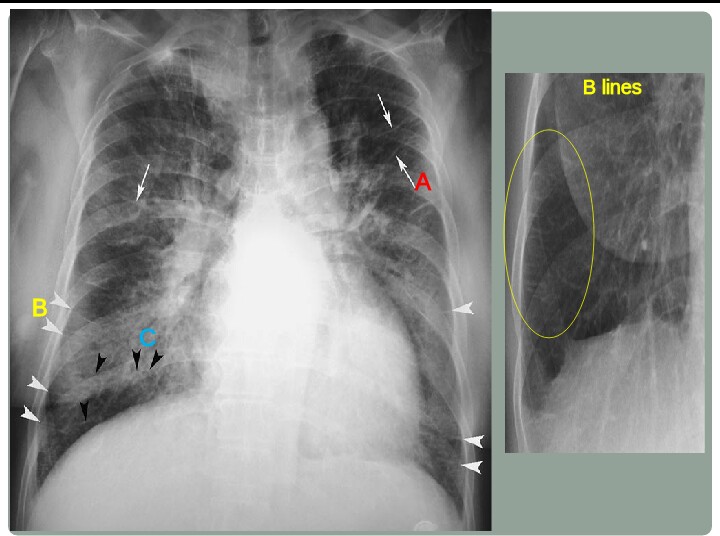

Unterschieden wird zwischen feinen, langen Kerley-A-Linien eher in den oberen Lungenabschnitten und kurzen, waagerechten Kerley-B-Linien, die in den unteren Lungenabschnitten nahe der Thoraxwand im so genannten costophrenischen Winkel verlaufen (vorwiegend rechtsseitig). Kerley-C-Linien sind spinnwebenartige Linien über der gesamten Lunge.